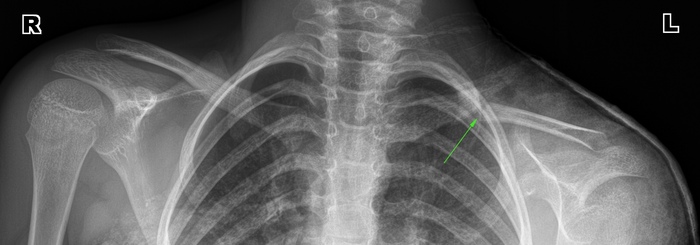

История 2. Перелом ключицы со смещением у ребенка

Травма случилась 6 марта, в предпраздничный день в детской больнице после рентгена сказали, что обычный перелом, смещения нет, наложили гипс и отпустили. Однако сегодня, 24 марта на контрольном снимке я вижу выраженное смещение каудального отломка книзу до 6 мм, ось кости деформирована углом, открытым книзу, до 40 градусов, Консолидация слабая. Рекомендую пока гипс не снимать, сходить к нормальному детскому травматологу-хирургу, наверняка он будет рекомендовать операцию с установлением пластины. Иначе срастется как попало, плечо будет ниже, испортится осанка и будет еще много разных проблем.